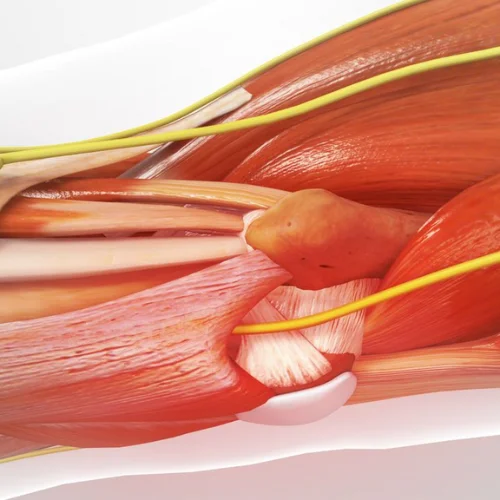

Hand and wrist surgery focuses on the diagnosis, treatment, and rehabilitation of conditions affecting the hand, wrist, and forearm. Whether caused by injury, arthritis, or repetitive strain, our expert orthopedic surgeons provide advanced surgical and non-surgical solutions to restore function, alleviate pain, and improve mobility.

This type of surgery, also called arthroplasty, is used in cases of severe hand arthritis. It is done by replacing a joint that has been destroyed by arthritis or injury with an artificial joint. This artificial joint may be made of metal, plastic, silicone rubber, or your own body tissue, such as a tendon.